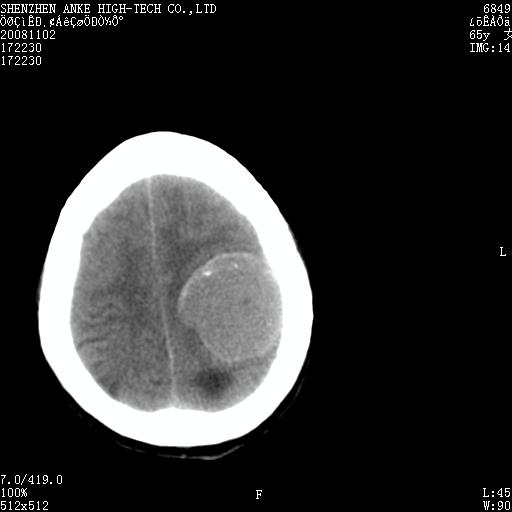

患者,女性,65岁,突发右侧肢体无力伴头痛,恶心、呕吐3小时.

1 左侧顶区圆形病灶,内可见钙化,考虑脑膜瘤,建议增强。2 左侧侧脑室病变,考虑神经上皮囊肿。

1)左侧顶区脑膜瘤可能性大;建议必要时行进一步检查。2)左侧脑室积水。

左顶部脑膜瘤,左侧侧脑室蛛网膜囊肿,建议增强.

左侧脑外占位(脑膜瘤)压迫脑实质、脑室侧室孔所致积水。支持!